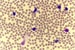

Initially intending to specialize in acute leukemias and bone marrow transplants, Joanna Rhodes, MD, MSCE, became drawn to the chronic lymphocytic leukemia (CLL) field after spending time in a CLL clinic and meeting patients at different stages of their journey.

Subsequent experience in the clinic led to a career in clinical research in CLL in order to improve treatment outcomes with targeted agents.